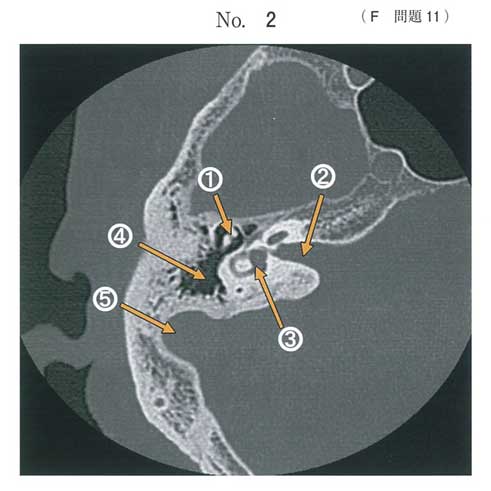

耳のCTが国試に出るんですね。自分は耳鼻科入局を決めるまで耳のCTの見方なんて全然知らなかったです。

①耳小骨

②内耳道

③前庭

④乳突蜂巣

⑤は何を指してるのかよくわからないです。小脳半球でしょうか?

正解はcでよいと思います。

頸静脈球です